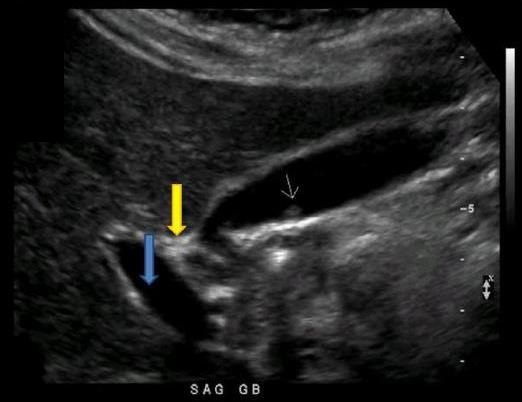

Which of the following statements is true regarding the image displayed?

The gallbladder has a normal variant called a Phrygian cap near the fundal area

What structure is indicated by the blue arrow?

Right portal vein

Which portions of the gallbladder and/or Billary tree are involved in the formation of a Phrygian cap?

Body and Fundus